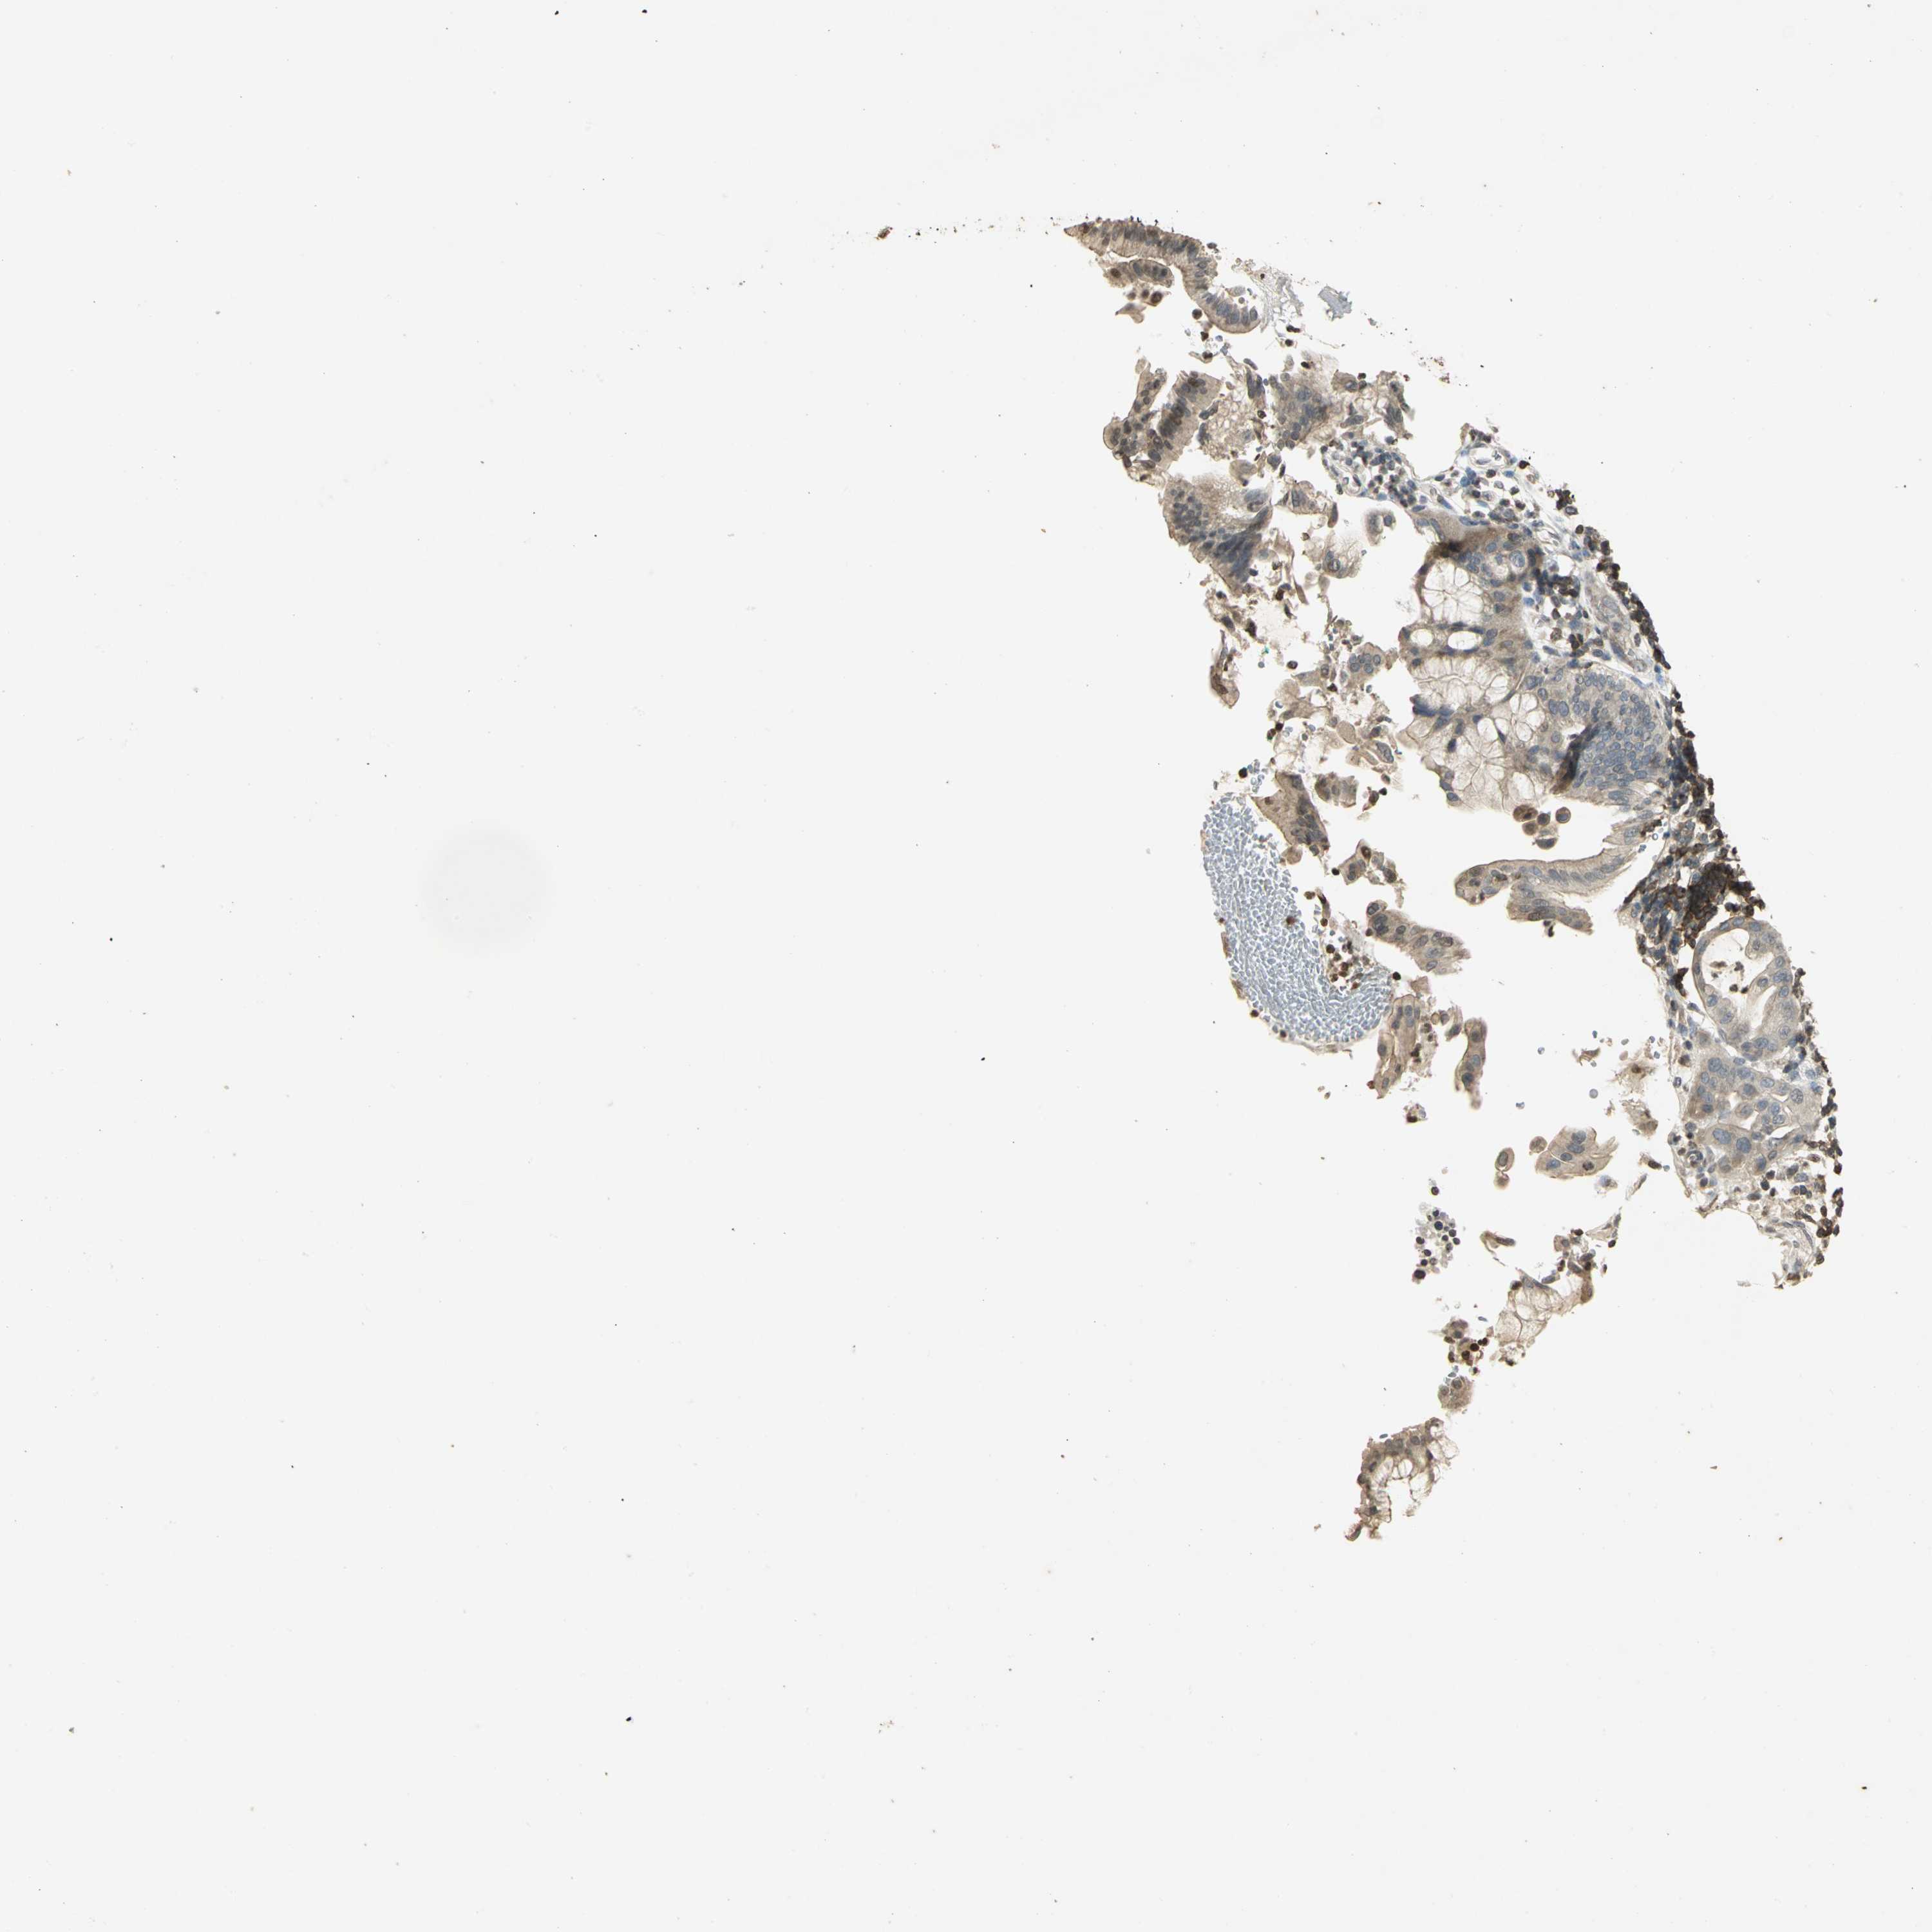

PANCREATIC CANCER - Protein expressioni

A mouse-over function shows sample information and annotation data. Click on an image to view it in a full screen mode. Samples can be filtered based on level of antibody staining by selecting one or several of the following categories: high, medium, low and not detected. The assay and annotation is described here.

Note that samples used for immunohistochemistry by the Human Protein Atlas do not correspond to samples in the TCGA dataset.

Antibody stainingi

Antibody staining in the annotated cell types in the current human tissue is reported as not detected, low, medium, or high, based on conventional immunohistochemistry profiling in selected tissues. This score is based on the combination of the staining intensity and fraction of stained cells.

Each image is clickable and will lead to virtual microscopy that enables deeper exploration of all samples and also displays staining intensity scores, fraction scores and subcellular localization as well as patient and tissue information for each sample.

Antibody HPA018467

Antibody CAB005247

Adenocarcinoma, NOS

Adenocarcinoma, metastatic, NOS